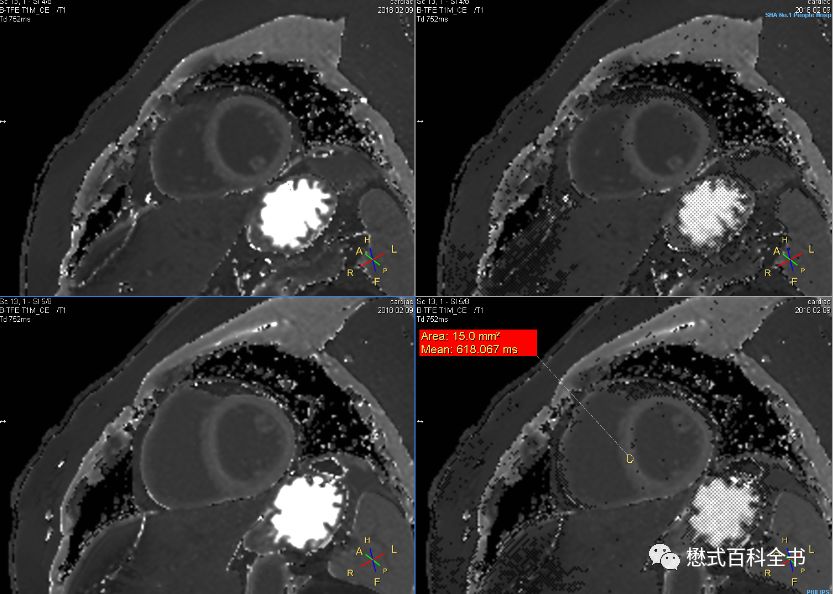

图12:心脏T1 mapping,Native T1

在进行心脏T1 mapping扫描中,一般会在打药前进行一次T1 mapping的扫描,叫做Native T1。

Native T1:初值T1值,也就是增强前测量的T1值,指心肌组织未给予对比剂情况下的纵向弛豫时间(T1)。

图13:心脏T1 mapping,Enhanced T1

打药后,也就是注射过对比剂后,理论上还应该扫描一次T1 mapping,这个时候的得到的T1值叫做Enhanced T1。

Enhanced T1:增强后T1值,也就是打药后测量的T1值,指心肌组织给予对比剂以后的纵向弛豫时间(T1)。

我们知道,磁共振对比剂会缩短组织的T1时间(也就是T1值),所以,打药前后测的T1值是完全不同的。

做了这个工作以后,在通过一些公式,我们主要是为了得到ECV。

ECV(Extracelluar Volume):细胞外容积,反映了未被心肌细胞占据的心肌组织分数。结合血细胞容积,Native T1及Enhanced T1,我们可以计算出ECV,并且得到ECV map。

同T2 mapping及T2* mapping一样,T1 mapping序列扫描完后,可以自动生成出T1 map图。

图15:Native T1图

图16:Enhanced T1图

扫描完Native T1或者Enhanced T1后,都会生成相应的T1 map。直接在T1 map图上划感兴趣区ROI即可测得该区域组织的T1值。